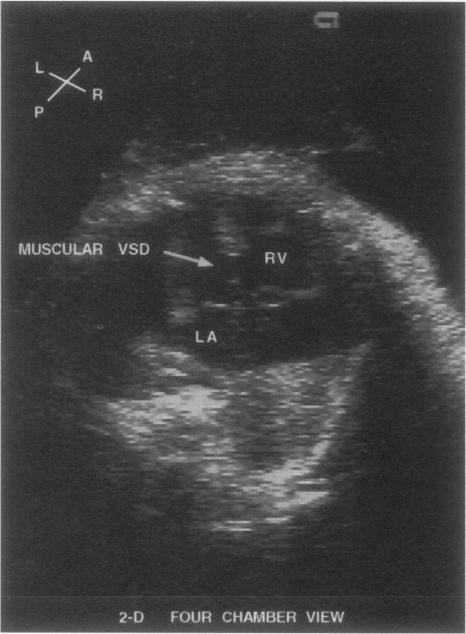

Fetal echocardiography is the primary modality for defining and evaluating fetal cardiac status and requires detailed analysis of the cardiac anatomy from numerous views and Doppler interrogation of the intracardiac structures, great vessels, and umbilical artery. Referrals for fetal echocardiography are determined by fetal, maternal, or familial risk factors; however, approximately 50% of neonates diagnosed with a congenital cardiac defect have no risk factor, and most have undergone an obstetrical ultrasound during the pregnancy that did not detect a cardiac defect. Advances in transducer technology have resulted in the development of small high-frequency transvaginal probes that allow fetal cardiac interrogation earlier during gestation. On the horizon is 3-dimensional fetal echocardiography, which provides rapid image acquisition and tremendous computer image reconstruction ability. At present, the computer image data analysis process is lengthy, and several technical limitations must be overcome before 3-dimensional fetal echocardiography becomes the primary modality of fetal cardiac imaging. New Doppler Tissue Imaging using color Doppler energy mapping allows more precise anatomic definition of the fetal endocardium, facilitating diagnosis of small ventricular septal defects. These new advances, along with improved image resolution, provide obstetricians and pediatric cardiologists with more tools and techniques for earlier and more precise detection of fetuses with cardiac defects.

胎儿超声心动图是确定和评估胎儿心脏状况的主要手段,需要从多个视角对心脏解剖结构进行详细分析,并对心脏内部结构、大血管和脐动脉进行多普勒检查。胎儿超声心动图的转诊由胎儿、母亲或家族风险因素决定;然而,约50%被诊断患有先天性心脏缺陷的新生儿没有风险因素,且大多数在孕期接受过产科超声检查,但未检测出心脏缺陷。换能器技术的进步促使了小型高频经阴道探头的发展,使得在孕期更早地对胎儿心脏进行检查成为可能。三维胎儿超声心动图即将问世,它能够快速采集图像并具备强大的计算机图像重建能力。目前,计算机图像数据分析过程冗长,在三维胎儿超声心动图成为胎儿心脏成像的主要手段之前,必须克服一些技术限制。使用彩色多普勒能量图的新型多普勒组织成像能够更精确地界定胎儿心内膜的解剖结构,有助于诊断小型室间隔缺损。这些新进展,连同图像分辨率的提高,为产科医生和儿科心脏病专家提供了更多工具和技术,以便更早、更精确地检测出有心脏缺陷的胎儿。